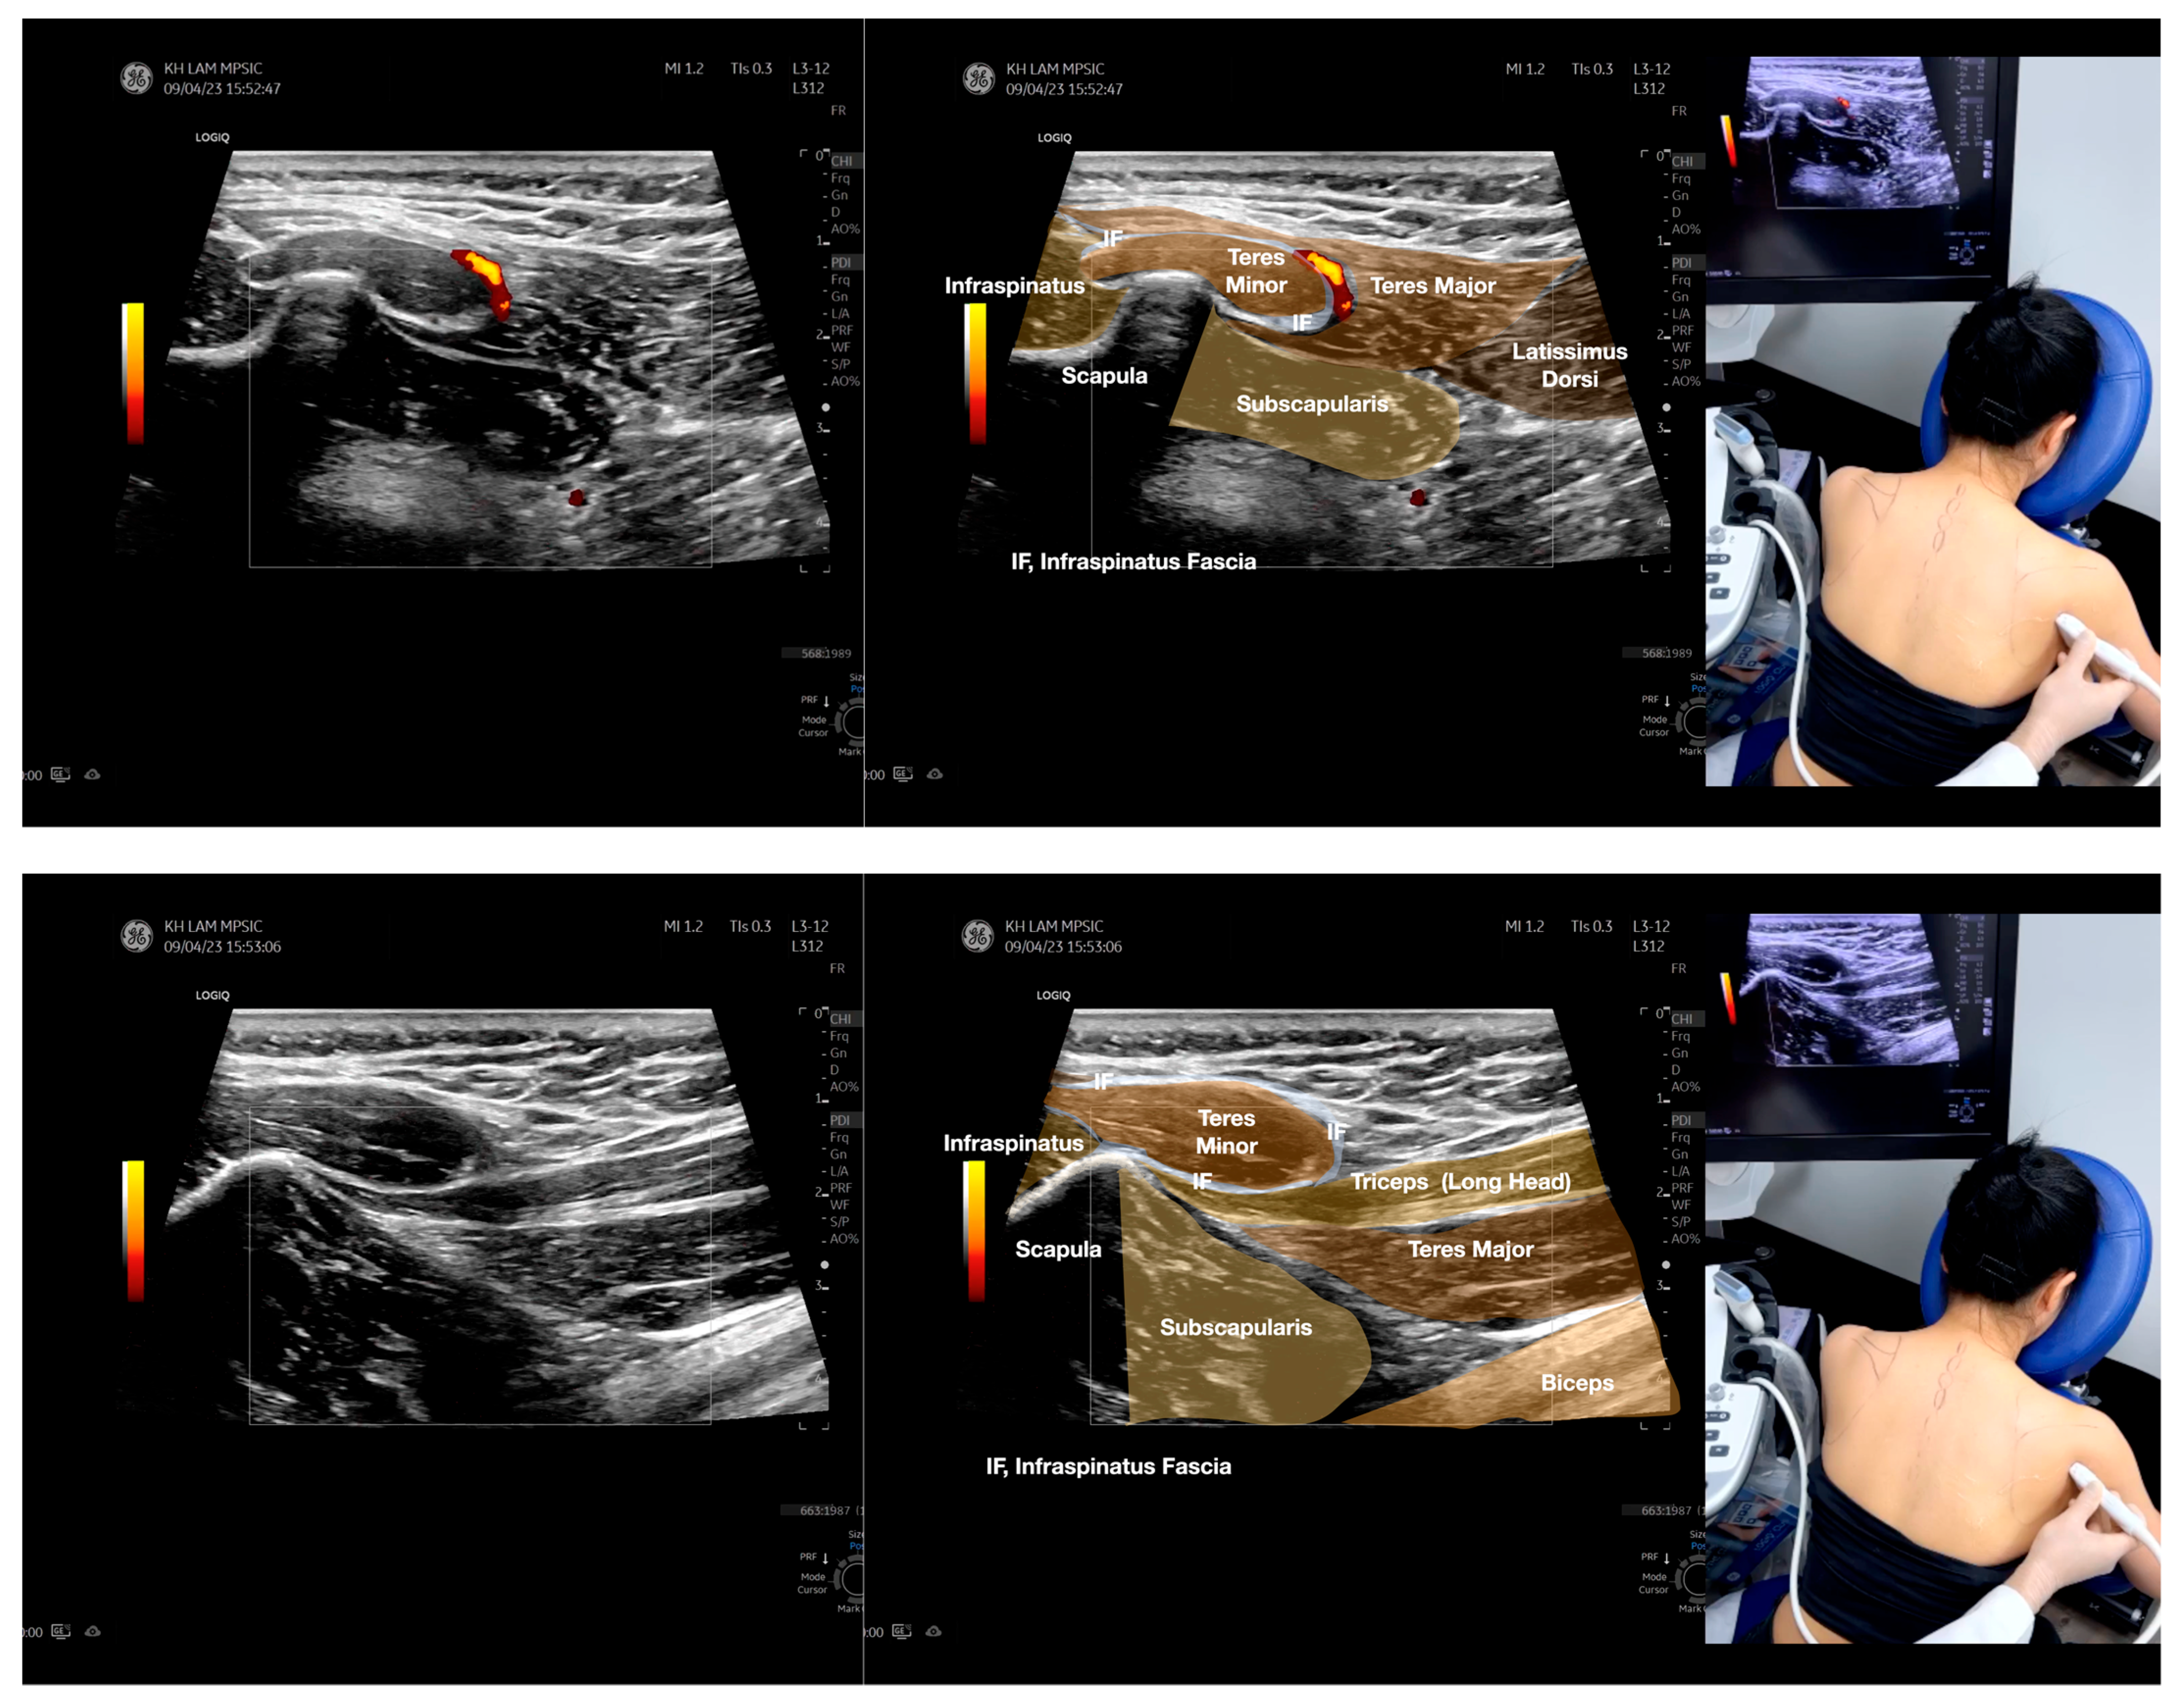

Figure 3.

Sonoanatomy of the lateral boarder of the scapular, its related muscles, and the infraspinatus fascia. Video S7 has demonstrated the step-by-step scanning techniques of these structures shown in this figure. Available online: https://www.dropbox.com/s/891m19vvw6bak34/Figure%203.docx?dl=0 (accessed on 1 January 2023).